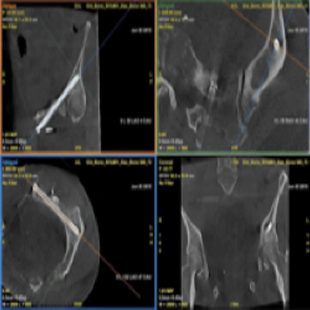

INTERVENTIONS OSSEUSES

Guider

Planifier

Évaluer